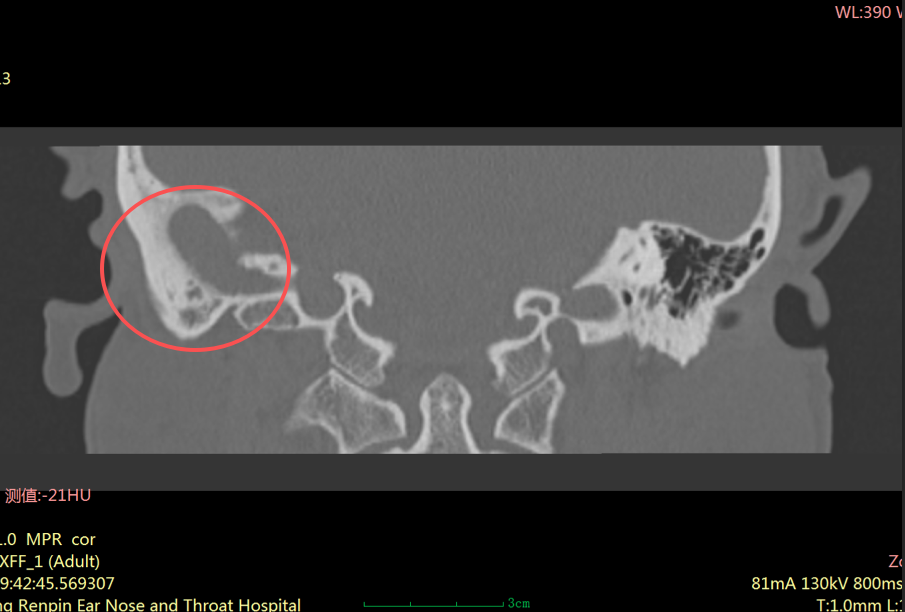

“患者右耳中耳腔已形成胆脂瘤,它像一颗不断侵蚀听骨的‘定时炸弹’,若再拖延,可能引发面瘫、颅内感染等严重并发症。”耳科主任张朝梅指着CT影像解释道。

胆脂瘤并非真正的肿瘤,而是中耳、乳突内形成的角化鳞状上皮堆积物。

虽然它不是肿瘤,但危害却不容小觑。它会像“寄生虫”一样,不断破坏周围的骨质,可能侵犯中耳的听小骨、面神经管、半规管等重要结构,进而导致听力下降、耳鸣、面瘫,严重时甚至可能引发颅内感染,危及生命。